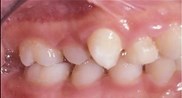

front view left buccal maxillary mandibular

Right Buccal View Frontal View Left Buccal View Maxillary View Mandibular View